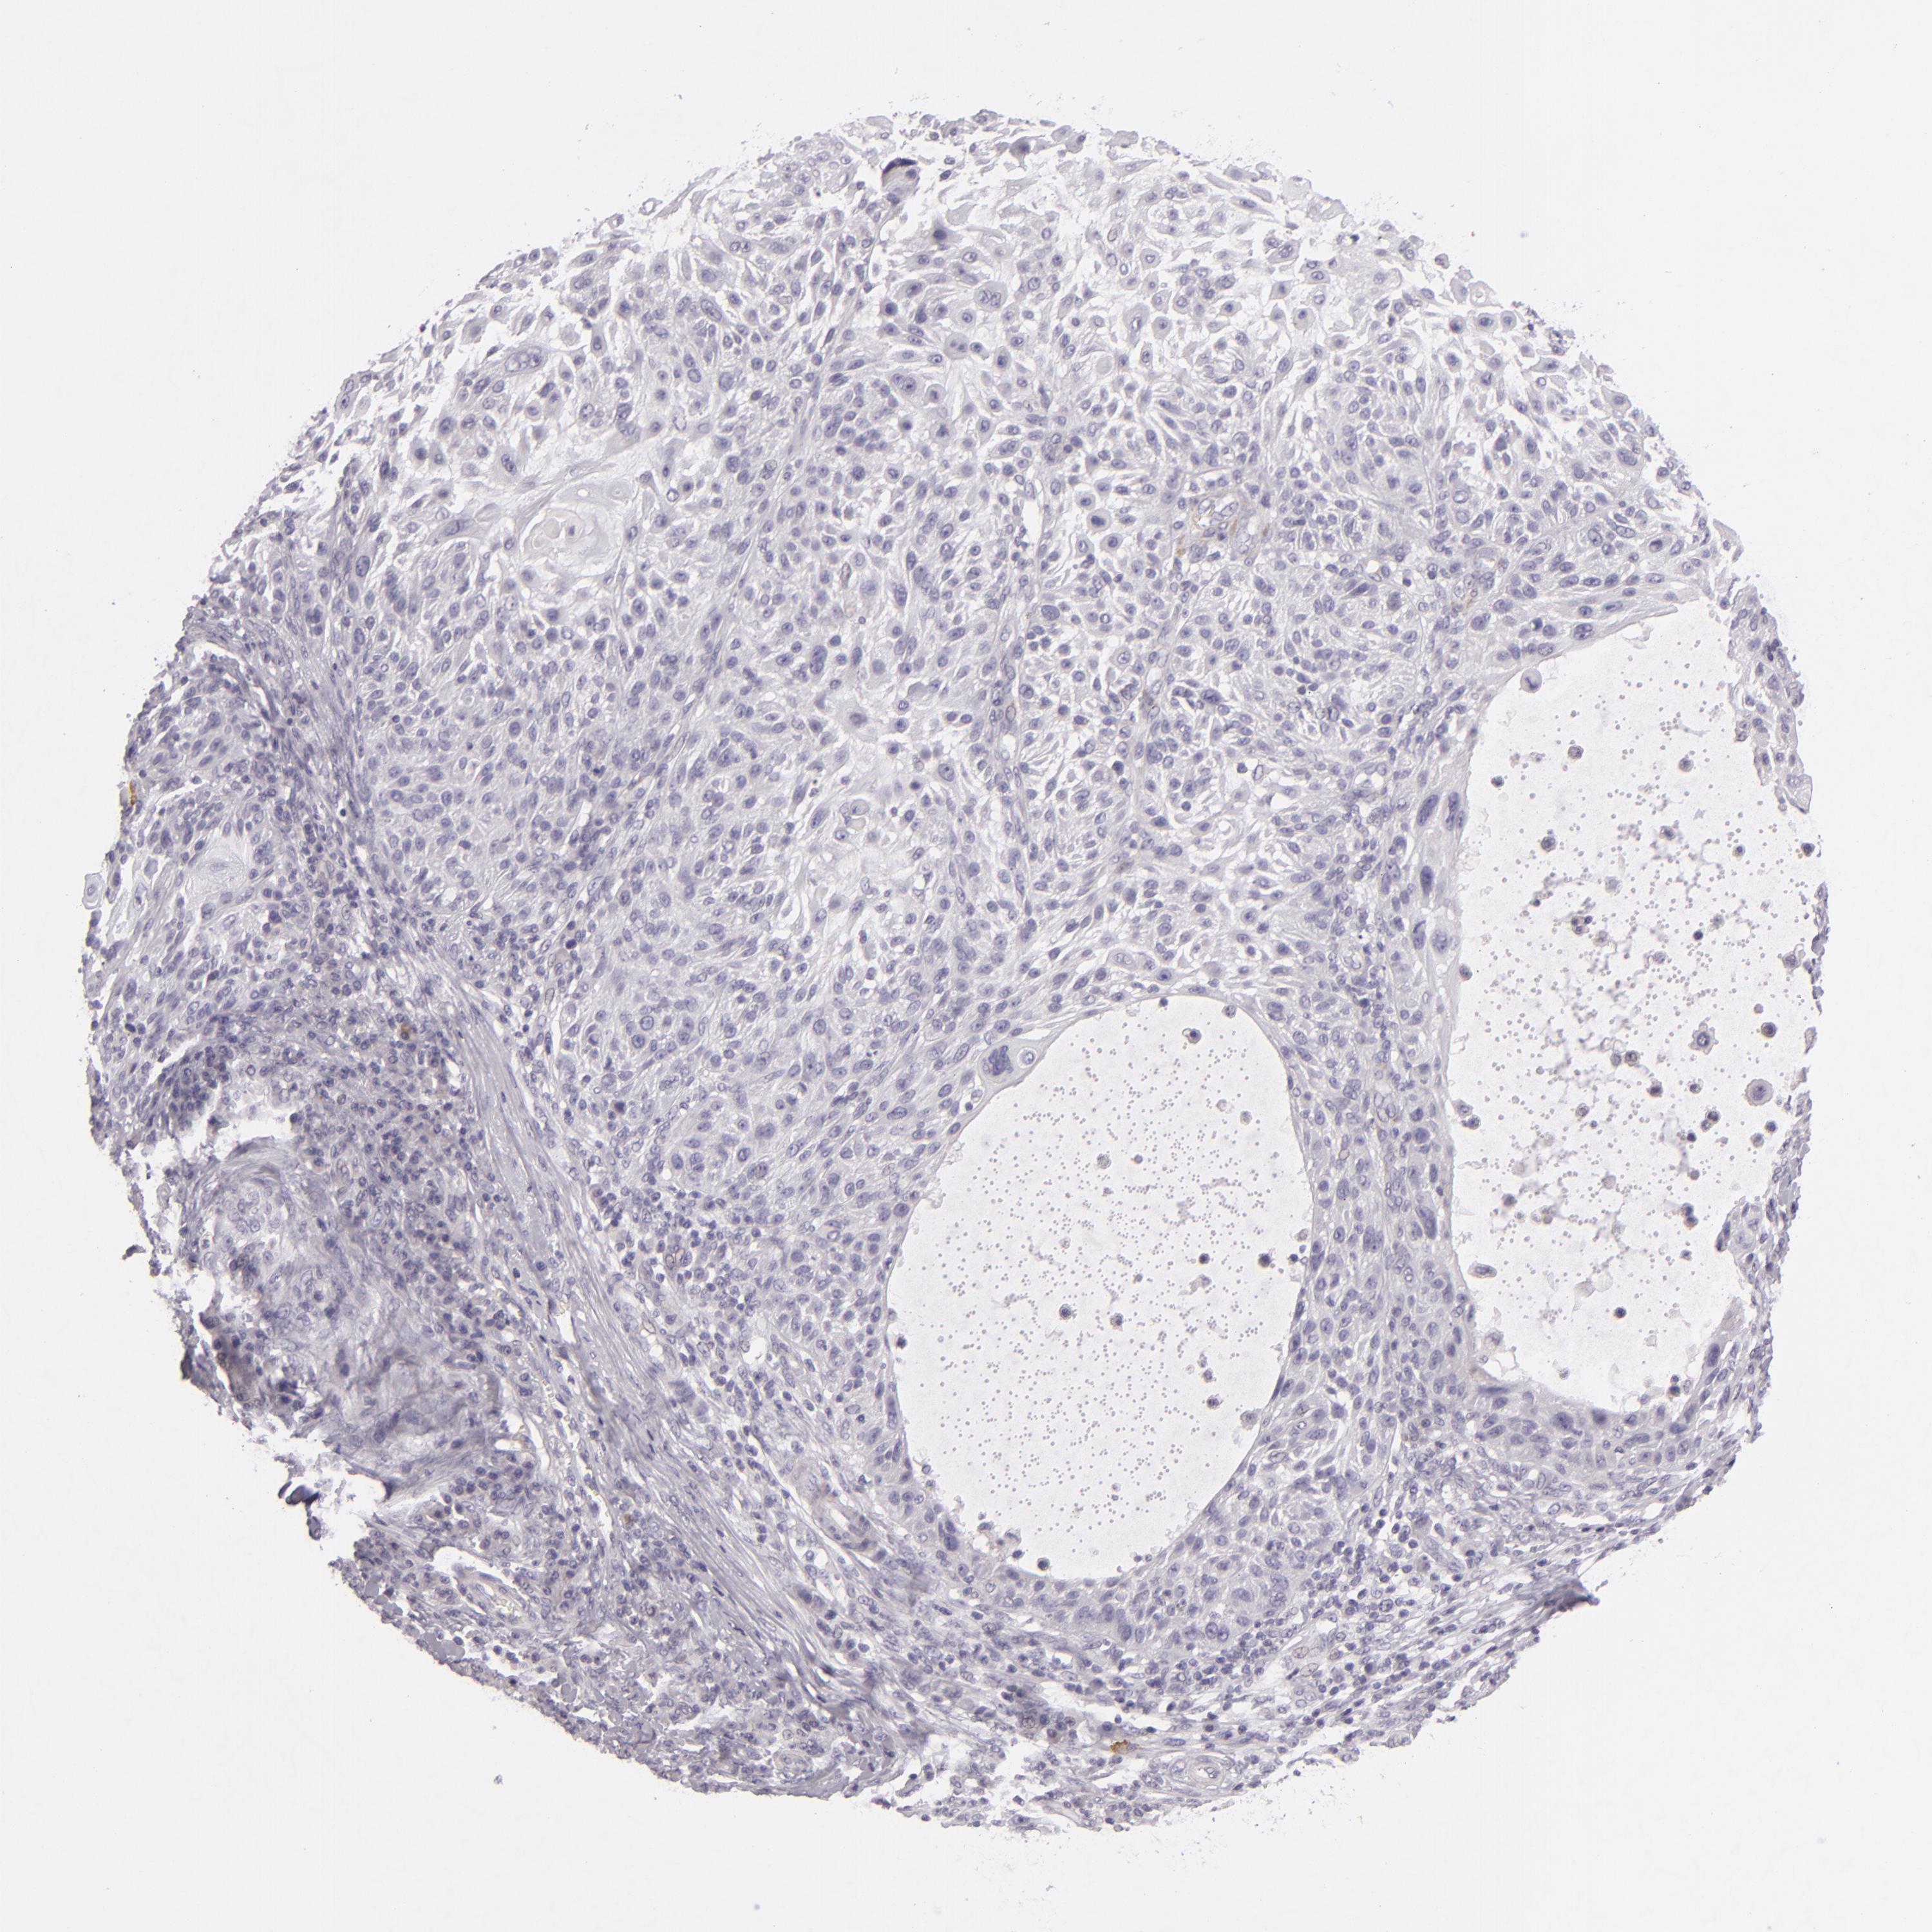

Basal cell and squamous cell cancer

SKIN CANCER - Protein expressioni

A mouse-over function shows sample information and annotation data. Click on an image to view it in a full screen mode. Samples can be filtered based on level of antibody staining by selecting one or several of the following categories: high, medium, low and not detected. The assay and annotation is described here.

Antibody stainingi

Antibody staining in the annotated cell types in the current human tissue is reported as not detected, low, medium, or high, based on conventional immunohistochemistry profiling in selected tissues. This score is based on the combination of the staining intensity and fraction of stained cells.

Each image is clickable and will lead to virtual microscopy that enables deeper exploration of all samples and also displays staining intensity scores, fraction scores and subcellular localization as well as patient and tissue information for each sample.

Antibody HPA001838

Squamous cell carcinoma, NOS

Basal cell carcinoma